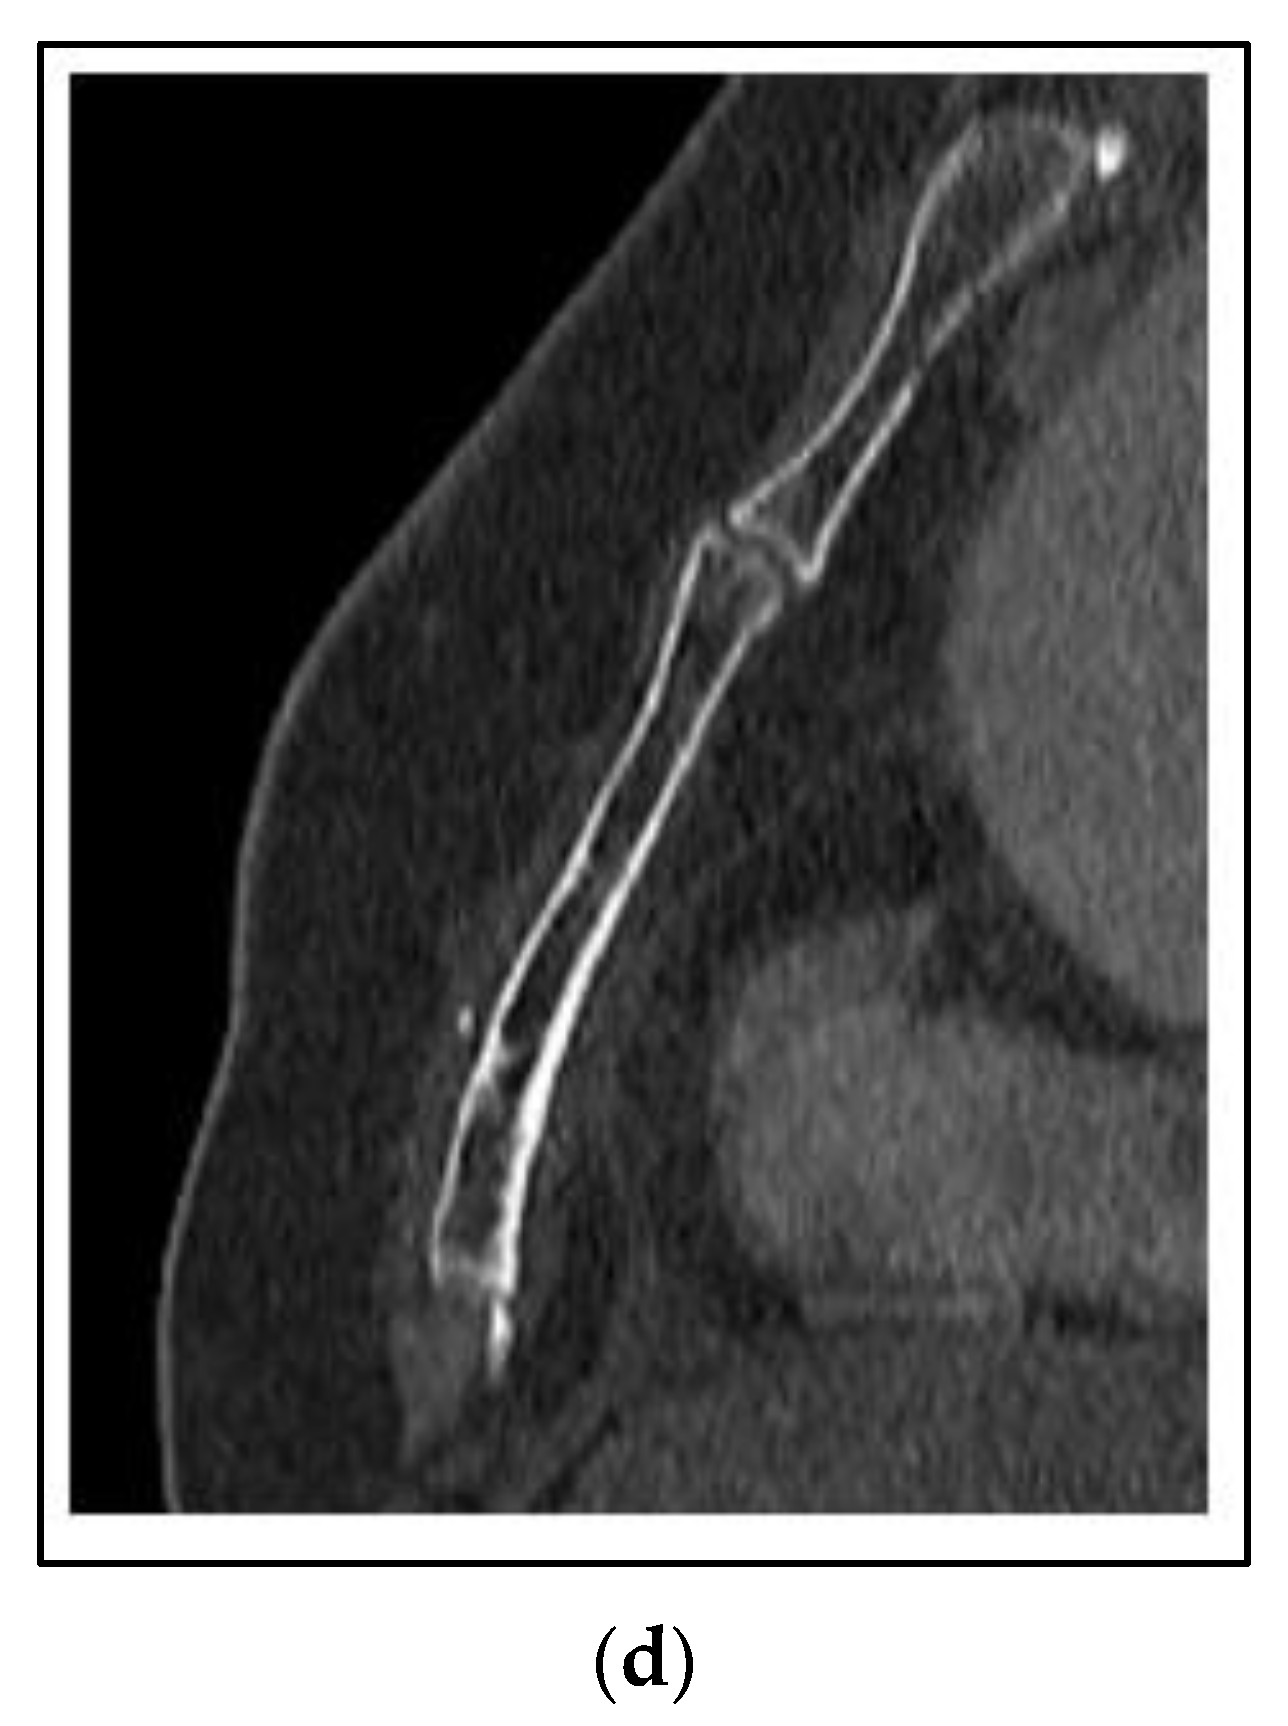

Cases 1–3 have been of synchronous or metachronous oligometastases. In a case of oligoprogression, there can be one or more limited number of sites of metastases that have not responded or progressed on a systemic regimen, while the others remain under control. Figure 5 shows a case of a 45 year old woman who presented with left breast cancer, clinical T1c N1 M0, ER+/PR+/HER2−, stage IB. She had neoadjuvant chemotherapy and bilateral mastectomy with flap reconstruction showing residual disease in the breast and axilla T1c (3) N2a. She was treated with adjuvant tamoxifen. After two years, she developed bone pain, and a bone scan was positive for an extensive number of metastases of the neck, ribs and spine. She was changed to leuprolide, aromatase inhibitor and CDK 4/6 inhibitor. However, within one year, she developed neck pain and an MRI and PET/CT showed a progression of the C1 vertebra. Her other disease was stable. She was treated with SBRT 24 Gy in 2 fractions. She had complete relief of her neck pain and continued on the same systemic therapy.

Figure 5. Case 4: Oligoprogression in the C1 vertebra. A 45-year-old woman presented with oligoprogression at C1 on systemic therapy for metachronous bone metastases. Representative images of the C1 metastasis on PET/CT (a) and MRI (b). (c) A colorwash image superimposed on a radiation planning CT showing the dose from SBRT to the C1 vertebral metastasis 24 Gy in 2 fractions with photon IMRT.